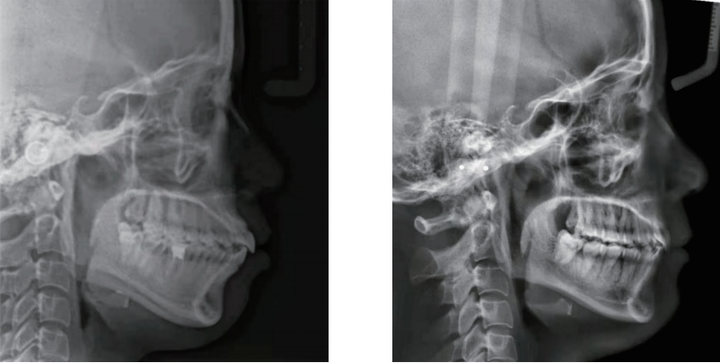

矫正行动:比如高角骨性下巴后缩,我们更多的希望是逆时针旋转,因此牙齿矫正过程中,我们要做好对上前牙的转矩控制,同时上牙不能过长,下前牙必须要足够的压低,并且是直立于基骨,这样可以下巴不会后退。

如果想要引导下巴往前伸,还需要控制好后部的颌平面角度,颌平面一定是平的,不能是倾斜的,如果颌平面越斜,会让下巴后缩。通过这三点来改变下颌骨的位置,从而可以改善下巴后缩的问题。

所以正畸医生做的就是这三点:上前牙的位置的控制,下前牙位置充分直立,还有颌平面的角度调整,通过这三点来改变下颌骨的位置,从而可以改善下巴后缩的问题。